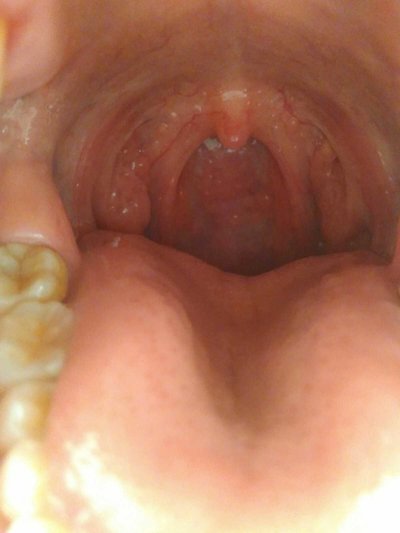

Rough tongue is actually a manifestation of ill health, which is related to the body fire, lack of vitamins, yin deficiency, strong stomach fire and other factors. If the patient has rough tongue due to this kind of disease, then usually the body will be accompanied by other abnormal symptoms, patients can judge their own cause through these symptoms. What's the reason for rough tongue coating? Let's talk about it

Inflamed is one of the most common diseases in our life. If we have this problem, it will not only make our tongue rough, but also accompanied by gingival bleeding, swollen throat and pain, yellow urine and other discomfort symptoms. In this case, we have to drink more water, eat more chrysanthemum, mung beans, cucumber, celery, Flammulina, tomatoes and other food to reduce the fire. If necessary, we can also take some heat clearing and fire removing drugs to eliminate the rough feeling of the tongue.